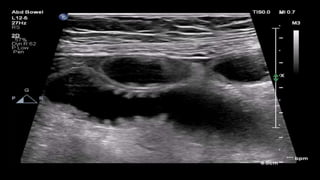

This document discusses the evaluation of right lower abdominal pain and lists appendicitis as a key cause. It notes that other potential causes include hemorrhagic cysts, heterotrophic pregnancy, salpingitis with pyosalpinx, funiculitis, and torsion of an undescended testis. The document was presented by Dr. A.S.M. Sufian of Cumilla Medical College Hospital and thanks the audience for their patience and listening.